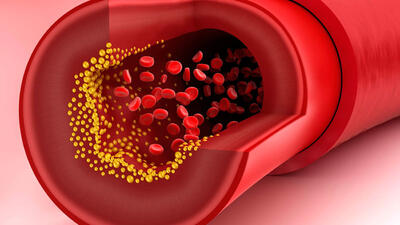

رگها را پس از سکته ترمیم می شوند

این ساختار سه بعدی مولکولهای درمانی را پس از سکته به مغز میرساند.

امیدی جدید برای درمان بیماری قلبی دیابتی

محققان کشف داروی دانشگاه موناش دریافتند که یک مولکول چربی طبیعی به نام